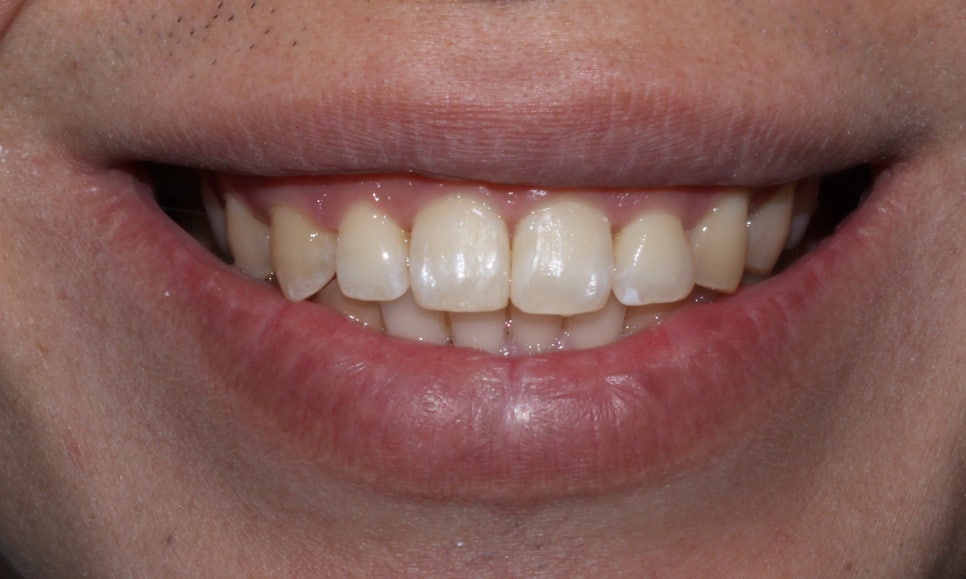

뻐드렁니 교정 후 입술의 모습을 보시면

교정 전과 달리 입술에서 돌출감이 사라진 모습인데요,

아무래도 앞니가 둘어가다 보니 입술도 튀어나온 부분 없이

바르게 자리잡힌 모습입니다.

미소를 지었을 때 보이는 앞니 역시

뻐드렁니 교정 후 돌출된 부분 없이

깔끔하게 교정된 모습입니다~

뻐드러짐이 가장 잘 보였던 측면의 사진 역시

교정 후 돌출감이 많이 완화된 모습입니다!

(+치아 사이에 끼어있던 치석도 깨끗하게 제거되었어요)

윗니가 아랫니를 많이 덮고 있어

과개교합 증상이 보였던 치아교합 역시

뻐드렁니 교정 후 바르게 교정된 모습입니다!

(+부분교정의 경우 전체교정보다 치아의 이동량이

적기때문에 드라마틱한 변화가 없을 수 있습니다)

앞니가 입술 방향으로 뻐드러져 있었던

교정 전 윗니와 달리 교정 후

치열이 가지런해지고 돌출감도 사라진 모습이에요^^

총생으로 들쭉날쭉하게 배열되었던

아랫니 역시 교정 후 치열이 가지런하고

바르게 교정된 모습입니다!